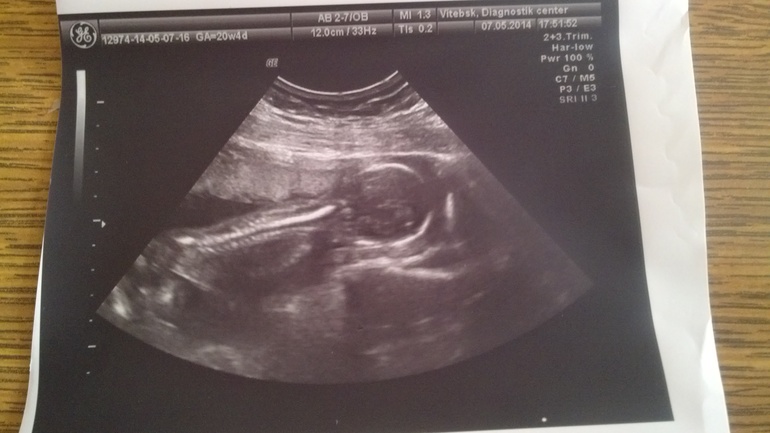

Тут нам уже 16 неделек